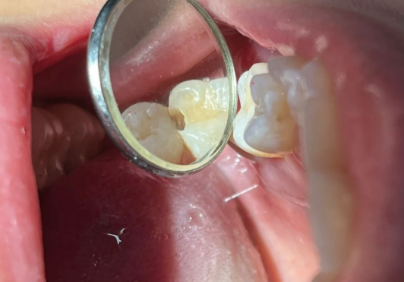

1、树脂补牙

树脂补牙是一种常见的补牙方式,适用于龋齿未伤及牙神经的情况。

国产树脂补牙:230元-500元/颗

进口树脂补牙:350元-800元/颗(例如美国3M、德国梅卡、日本松风等)

金属嵌体补牙:800元-1500元/颗

烤瓷嵌体:1500元/颗起

全瓷嵌体:2500元-4000元/颗